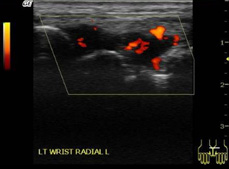

在類風(fēng)濕關(guān)節(jié)炎中,超聲在檢測關(guān)節(jié)炎癥方面優(yōu)于臨床檢查,可用于類風(fēng)濕關(guān)節(jié)炎與其他關(guān)節(jié)炎的鑒別診斷。即使滑膜炎處于臨床緩解期,超聲也能檢測出來??捎糜趤喤R床炎癥和治療反應(yīng)的評(píng)估。超聲檢查可發(fā)現(xiàn)滑膜炎、腱鞘炎和糜爛、積液、骨侵蝕的存在,預(yù)測關(guān)節(jié)損傷,并可用于評(píng)估預(yù)后。

類風(fēng)濕關(guān)節(jié)炎的手腕(滑膜炎)